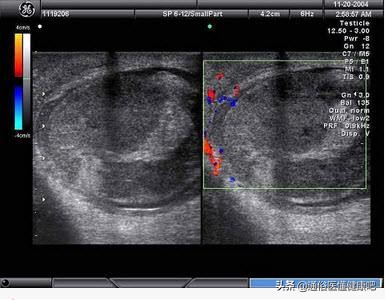

先以影像检查比如B超确认肿瘤的存在,并检查血中肿瘤标记物,如怀疑癌症,以手术切除作病理诊断,确认为癌症后,须进行电脑断层或核磁共振等,以了解是否扩散至淋巴、肺部或其他器官,再作后续治疗或追踪的规划。